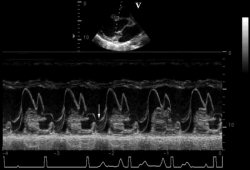

Prolapso posterior da valva mitral no ecocardiograma em modo M

Do acervo de Samir Kapadia e Mehdi H. Shishehbor

Veja esta imagem em contexto nas seguintes seções:

Regurgitação mitral